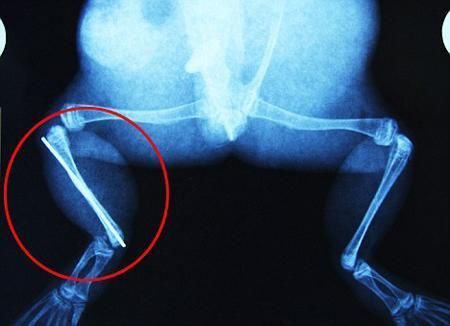

布魯萊的主人,居住在南非約翰內斯堡附近的62歲的安妮·米恩斯說:“我對這只青蛙如此關心,人們一定認為我瘋了,但是我無法眼睜睜看著它那么痛苦。青蛙因其靈活的腿腳而著稱,一想到布魯萊的腿里要留下一個薄金屬片,我就感到心痛。然而我知道,如果不進行手術,布魯萊以后就沒辦法動彈了。因此我匆匆趕到獸醫那里,央求他給這只可憐的青蛙動手術。這位獸醫整天救助小貓小狗,他很難理解為什么我這么擔心一只青蛙,但是最終他還是答應了給布魯萊做手術。手術后是幾個小時的焦急等待,我們希望它能快快蘇醒過來。不過現在它的傷口已經愈合,又能在花園里跳來跳去了。X光照射顯示,它會恢復的跟以前一樣。”

野生生物專家安妮經常為學校寫教材,她認為這是人類第一次通過手術給一只青蛙接斷腿。在手術開始階段,獸醫把少量給狗用的麻醉藥注入到這只青蛙體內,讓它失去知覺。然后他在布魯萊的斷腿上切開一個小口,把一根小鋼針植入腿里。最后獸醫給它縫了9針,把切口縫合在一起。僅僅幾周后,布魯萊就能在安妮家附近活動了。這只青蛙大約已有25歲,主要以嚙齒動物、蛇和其他青蛙為食。布魯萊所屬的牛蛙種群正在不斷減小,目前只能在非洲南部的濕地里才能看到這種青蛙。